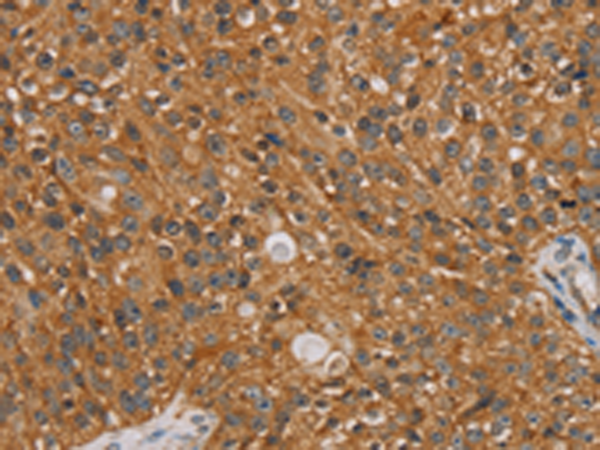

分类: 科研抗体货号: P01580别名: B8; CD14; CIB8; MC1DN13应用: WB,IHC反应种属: Human, Mouse